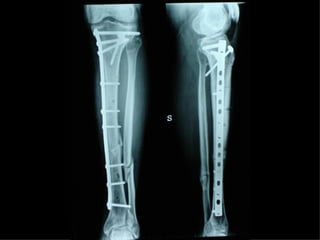

Dal Gennaio 2000 al Febbraio 2006 abbiamo trattato 167 fratture chiuse  con placca percutanea  in 164 pazienti :  27 lesioni diafisarie di gamba, 12 piloni tibiali ,  11 fratture prossimali di tibia, 36 fratture sovracondiloidee di femore, 17 fratture diafisarie di femore, 43 fratture metaepifisarie prossimali di omero, 21 diafisarie d’omero.  156 guarigioni 8 fallimenti

Dal Giugno 2002 al Dicembre 2004 abbiamo trattato 5 fratture esposte: 3 di tibia e 2 di ulna 5 guarigioni

I buoni risultati ottenuti dipendono da 5 punti fondamentali:   una accurata riduzione percutanea della frattura  precise vie di accesso  l’utilizzo della placca che consenta il più lungo braccio di leva possibile il pretensionamento della placca  una sintesi con un ridotto numero di viti

Accurata riduzione percutanea della frattura

Precise vie di accesso

Placche lunghe e pretensionate

Placche lunghe e pretensionate Sintesi con un ridotto numero di viti

2 Insuccessi

Fratture  esposte